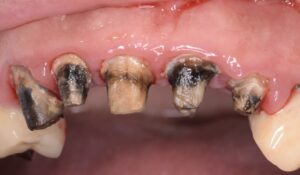

また、大きく削って被せ物をしないと治療報酬的に赤字になるということで、本当に大事な部分を削っては金属で被せてきました。歯を守るための理論を完全に無視した治療(破壊行為?)が平然と行われているのが現状です。そうしないと医院経営ができないような健康保険のシステムが悪いと考えていますが、安かろう悪かろうで通用していました。その結果、上の写真のように、被せ物の縁からは細菌がドバドバ入り、外すと歯がボロボロという悲しい状況がつくられてしまいました。被せ物は丈夫なので、外からはわからないけど、中は腐ってグジュグジュ、という歯を何千本見てきたことでしょう